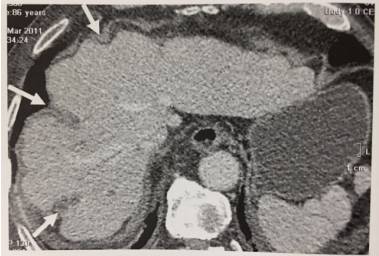

10、肝多发副裂

肝膈面多发伸入肝实质的裂痕。